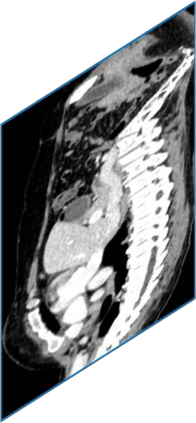

Due to the constraints of the imaging device and high cost in operation time, computer tomography (CT) scans are usually acquired with low intra-slice resolution. Improving the intra-slice resolution is beneficial to the disease diagnosis for both human experts and computer-aided systems. To this end, this paper builds a novel medical slice synthesis to increase the between-slice resolution. Considering that the ground-truth intermediate medical slices are always absent in clinical practice, we introduce the incremental cross-view mutual distillation strategy to accomplish this task in the self-supervised learning manner. Specifically, we model this problem from three different views: slice-wise interpolation from axial view and pixel-wise interpolation from coronal and sagittal views. Under this circumstance, the models learned from different views can distill valuable knowledge to guide the learning processes of each other. We can repeat this process to make the models synthesize intermediate slice data with increasing inter-slice resolution. To demonstrate the effectiveness of the proposed approach, we conduct comprehensive experiments on a large-scale CT dataset. Quantitative and qualitative comparison results show that our method outperforms state-of-the-art algorithms by clear margins.